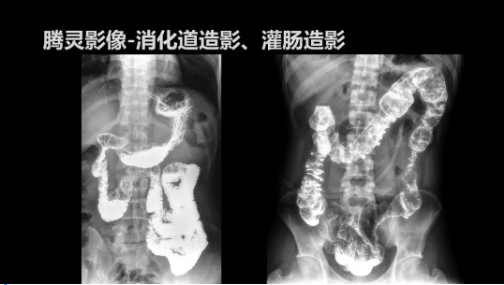

“騰靈”是安健科技的第四代動態(tài)DR產(chǎn)品,可實現(xiàn)全科室應用。如各類常規(guī)的X線檢查、消化道檢查、骨科檢查、婦科、兒科檢查等。此外,安健科技為“騰靈”在真正意義上實現(xiàn)多科室、多功能診斷進行了多項針對性設計。